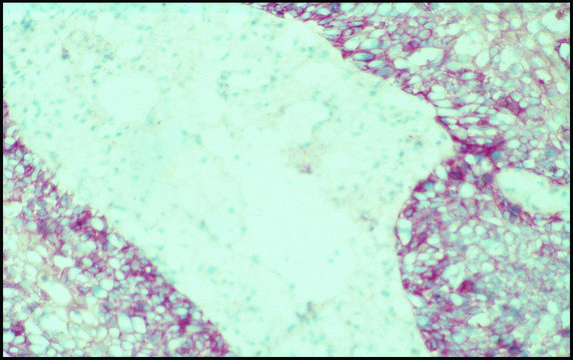

immunohistochemistry (formalin-fixed, paraffin-embedded sections): suitable, immunohistochemistry (frozen sections): suitable, immunoprecipitation (IP): suitable, indirect ELISA: suitable, microarray: suitable, western blot: 1:2,000

• immunohistochemical staining

To evaluate a possible association between clinical outcome in patients with glioblastoma and expression of some immunohistochemical variables and apoptosis. 168 selected patients with cerebral glioblastomas were studied retrospectively. Tumour specimens were examined immunohistochemically with antibodies to proliferating cell nuclear